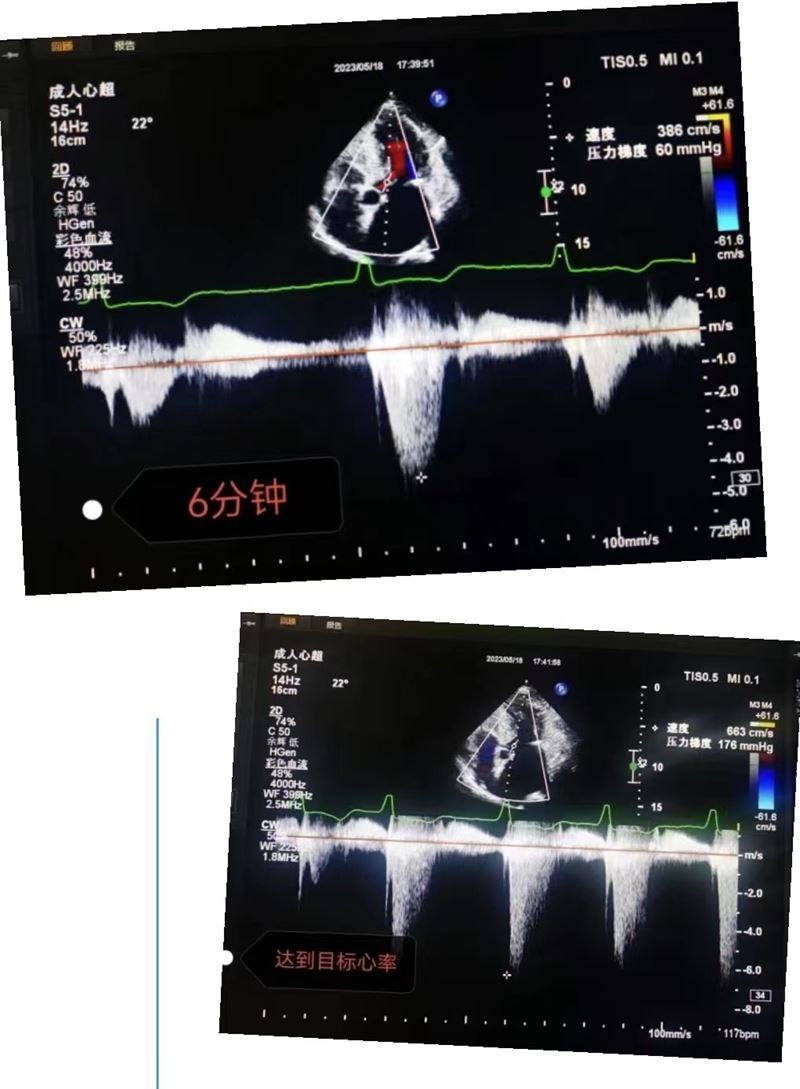

超聲科王英莉主任及心血管組賈貝主治醫(yī)師、陳輝主管護(hù)師及牛丹青護(hù)師為該患者行藥物負(fù)荷超聲心動(dòng)圖。監(jiān)護(hù)儀、急救車到位,常規(guī)經(jīng)胸超聲心動(dòng)圖提示室間隔增厚,左室流出道血流速度略增快,左心腔超聲造影,可清晰顯示室壁顯著增厚,符合肥厚型心肌病表現(xiàn),隨后又進(jìn)行了多巴酚丁胺負(fù)荷超聲心動(dòng)圖,靜息狀態(tài)下顯示左室流出道血流速度V:207cm/s,PG:17mmHg;3分鐘后心率達(dá)75次/分,左室流出道血流速度V:218cm/s,PG:19mmHg;6分鐘后心率達(dá)94次/分,左室流出道血流速度V:386cm/s,PG:60mmHg;9分鐘后達(dá)到目標(biāo)心率,左室流出道血流速度V:649cm/s,PG:169mmHg,停止用藥,藥物負(fù)荷試驗(yàn)陽性,檢查過程中患者無不適癥狀,最終診斷為隱匿性肥厚型梗阻性心肌病。